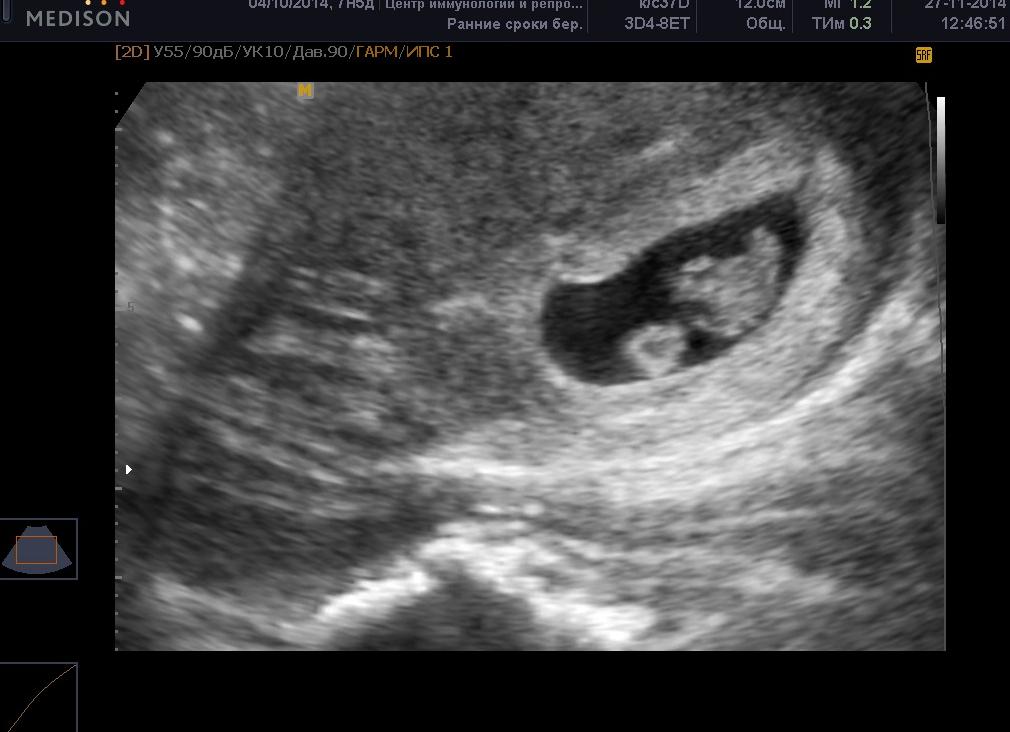

Как выглядит двойня на УЗИ?

Увидеть двойняшек на мониторе при ультразвуке можно начиная с самых ранних сроков. В это время малыши только-только начинают оформляться, и на экране видно просто 2 темных пятнышка. Но у каждого из них уже есть маленькое сердечко, которое вполне реально услышать.

Если будущая мама впервые узнала о двойняшках на первом плановом ультразвуке в 9-11 недель, она может увидеть полноценных эмбрионов длиной в 4,5-4,8 см. Малыши в это время уже двигаются, у них сформированы внутренние органы, появились пальчики. К 14-й неделе плоды уже достигают в длину 12 см – в это время мамин животик начинает активно расти. В 12 недель длина каждого из близнецов – около 6 см, вес – приблизительно 8 гр.

Уже в начале второго месяца обозначается двойня. На том сроке врач может подтвердить не только присутствие эмбриона, но и обозначить присутствие сердечных сокращений, подтвердить, что он жизнеспособен. В этот период в 80 процентов случаев, определяема многоплодность. Двойня в таком временном промежутке имеет вид темных пятен, расположенных в маточной полости.